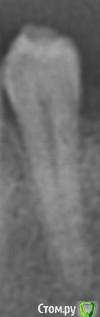

aleefsd Опубликовано 5 марта, 2016 Автор Поделиться Опубликовано 5 марта, 2016 вот снимок Ссылка на комментарий

shishok Опубликовано 6 марта, 2016 Поделиться Опубликовано 6 марта, 2016 пломба всё это прикрывает, закрывает обзор? Или такое невозможно?Как определить пульпит и возможно ли это ? Ренген снимок могу конечно выложить, но по нему можно ли определить пульпит?На снимке можно обнаружить вторичный кариес под пломбой(и его размер).Пульпит по снимку не определить.Нужны дополнительные методы. Ссылка на комментарий